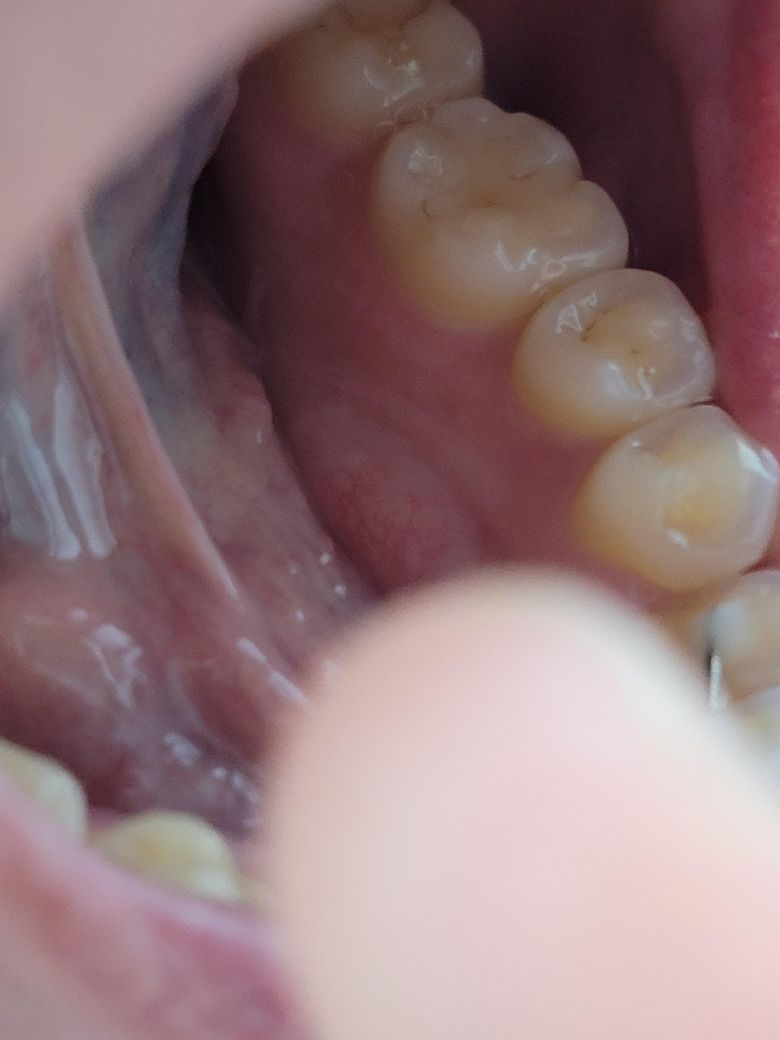

엑스레이는 한달이 지난 거여서 방금 찍은 치아사진도 첨부합니다

• 1번 째 사진